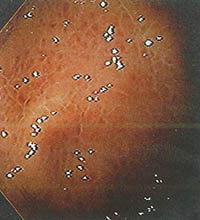

ΕΝΔΟΣΚΟΠΙΚΗ ΕΜΦΑΝΙΣΗ HELICOBACTER PYLORI ΓΑΣΤΡΙΤΙΔΑΣ

Η χρόνια Helicobacter pylori γαστρίτης δεν έχει διακριτό ενδοσκοπικό πρότυπο, το οποίο εξαρτώμενο από το στάδιο ή την κατανομή· υπεραιμία, διαβρώσεις, εξελκώσεις υπερτροφία και ατροφία μπορεί να συνυπάρχουν σε ποικίλους συνδυασμούς στον ίδιο στόμαχο και σε εμφανώς φυσιολογικές περιοχές. Επίσης, κανένα από αυτά τα χαρακτηριστικά δεν είναι χρήσιμα για την πρόβλεψη της παρουσίας ή απουσίας της χρόνιας λοίμωξης από το μικρόβιο Helicobacter pylori. Συνεπώς, η διάγνωση της Helicobacter pylori γαστρίτιδας απαιτεί ιστοπαθολογική ανάλυση.